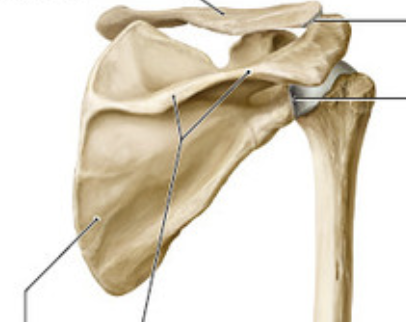

Landmarks of the scapula include the __, the __ process, __ and __ angles, the __ and __ and lateral borders

Landmarks of the scapula include the acromion, the coracoid process, superior and inferior angles, the spine and medial and lateral borders

The scapula is a flat triangular bone that forms the posterior part of the pectoral girdle

It overlies the 2nd to 7th ribs on the posterior thoracic wall.

It has __, __, and ___ borders and a __ and __ angle.

Laterally, a shallow depression, the ___ cavity, articulates with the humerus.

A narrow neck separates the glenoid cavity from the large body of the scapula.

A ___ fossa lies on the anterior surface against the rib cage.

The spine of the scapula on the posterior surface separates the supraspinous and infraspinous fossae. Laterally, the spine expands to form the acromion.

A ___ process extends anteriorly and superiorly over the glenoid cavity.

The scapula is a flat triangular bone that forms the posterior part of the pectoral girdle (Figs. 13.4 and 13.5).

It has medial, lateral, and superior borders and a superior and inferior angle.

Laterally, a shallow depression, the glenoid cavity, articulates with the humerus.

A subscapular fossa lies on the anterior surface against the rib cage.

A coracoid process extends anteriorly and superiorly over the glenoid cavity.